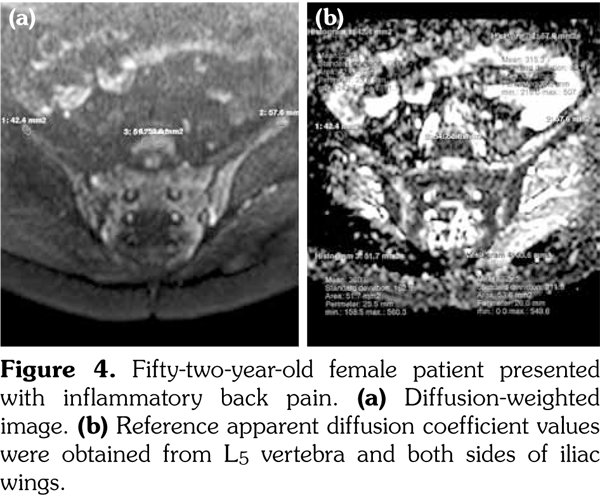

Sacroiliac joints were assessed according to ankylosing spondylitis criteria. Before evaluation of standard MRI protocol, patients’ information was removed from images. Afterwards, two experienced radiologists evaluated the images for the presence of inflammatory activity twice at separate sessions to assess interobserver variability. Following the examination of T2-weighted SPIR, contrast- enhanced T1-weighted SPIR, and DWIs at b values of 600 s/mm2, two radiologists and rheumatologists reached a consensus on the disease activity in the light of positive features of Berlin criteria. The DWIs were transferred to a separate workstation (Phillips, Extended MR workspace, 2.6.3.2.HF3, Netherlands). ADC maps were generated. T2-weighted SPIR images, contrast-enhanced images and diffusion-weighted images with ADC maps were put on the screen side by side. In the disease group, the hyperintense lesions on T2-weighted SPIR images and enhanced focuses on contrast- enhanced images were noted and the same lesions were marked on DWI images and ADC map. A circular ROI with a range of 40-75 mm2 was placed in those areas. In the control group a circular ROI was placed in the subarticular area of joints. Also, the same process was performed for the normal-appearing bone marrow areas near the joints of the disease group (Figure 2). Four standard measurements were conducted from each joint, including two on sacral and the other two on the iliac side for all patients (Figure 3). Additionally, two measurements were conducted from the fifth lumbar vertebra and one from each iliac wing (Figure 4). All measurements were performed twice. ADC values were expressed as square millimeters per second. The r-ADC ratio was calculated by dividing ADC value of subchondral bone or inflammatory lesions to ADC values of the fifth lumbar vertebra and iliac wings.